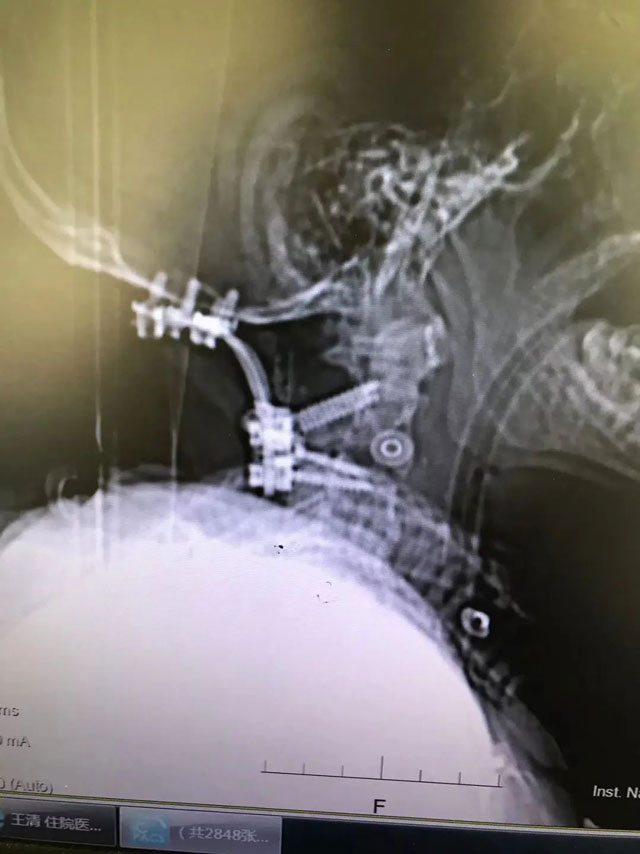

术后

一周前,在西南医科大学附属医院脊柱外科王清教授的带领下,医院首例也是脊柱外科界难度系数较高的手术——颈后方寰枢椎侧方入路脊髓前方肿瘤切除脊髓解压术和枕颈固定术顺利完成。

王清说,这是他从业几十年来遇到的最难的一次手术。耗时7小时,最终他带领脊柱外科手术团队攀越了脊柱外科手术的“高峰”,顺利完成手术。目前,王大爷的病情有了好转,还在进一步恢复中。